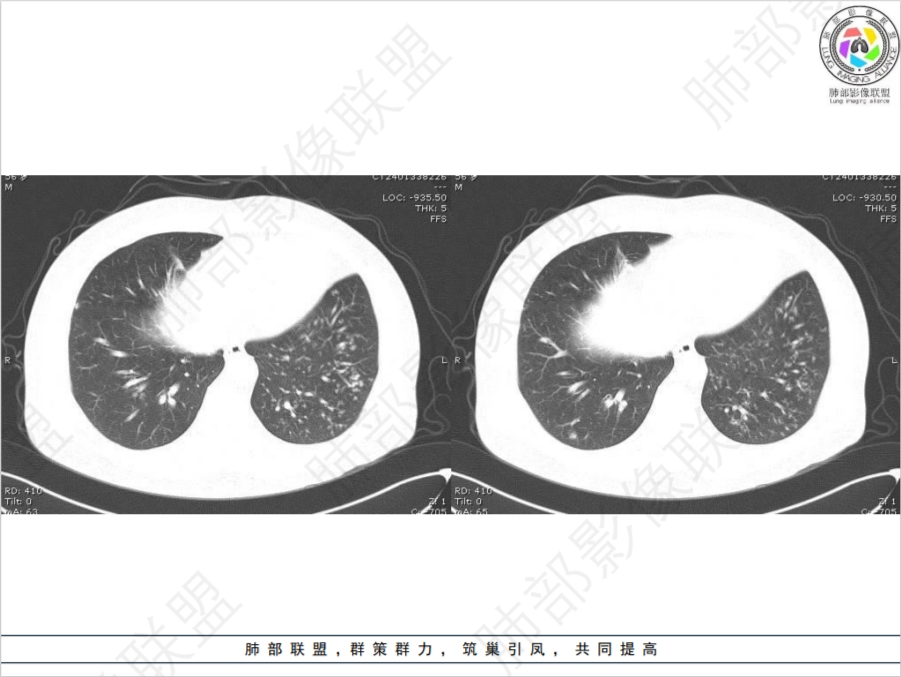

病灶多灶性,多态性,这个病例如何确诊肺结核?

肺结核的ct影像表现特点多样且复杂: